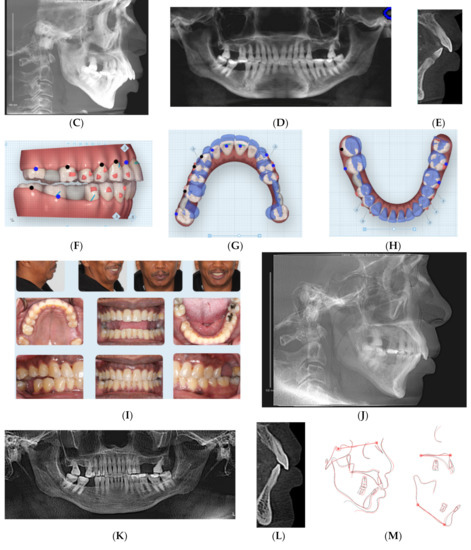

This 47-year-old male presented with chief concerns including correcting his crowded teeth (upper arch 5 mm and lower arch 4 mm arch length deficiencies), increased overjet (7 mm), and improving his recessive chin without surgical intervention, if possible. The patient was also not interested in regular fixed appliance. Clinical records (Figure 2A–E) revealed a convex profile with recessive/double chin, skeletal Class II apical base relationship (ANB = 9°) with high mandibular plane angle (FMA = 35°), and compensated upper and lower incisors (U1 NA = 6 mm; U1-SN = 98°; LI NB = 11.3 mm; L1MP −99°). Intraoral photographs and the panoramic radiograph reveal a missing upper right second molar, upper left first and second molars, and lower right first molar. In addition, both panoramic and cephalometric radiographs (Figure 2C,D) reveal a short mandibular ramus and body as well, which makes non-surgical treatment of the case more challenging. Figure 2E shows the crown-root ratio of lower incisors more than 1:1 with thin alveolar bone labio-lingually, which makes it very difficult or risky to move the lower incisors enough to minimize lower arch crowding or minimize overjet should camouflage treatment be proposed.

Figure 2.

(A) Initial photographs showing convex profile with recessive chin and anterior crowding. (B) Initial digital models showing left side Class II buccal occlusion with a 7 mm increased overjet. (C) CBCT-driven cephalometric radiograph showing convex profile with recessive chin and protrusive upper incisors. (D) CBCT panoramic radiograph showing missing 1.7, 2.6, 2.7, and 4.6 molars; no other noticeable intraoral bony lesion could be detected. (E) CBCT-driven sagittal screen of lower incisor showing its severe proclination with minimum bone appears on most of the labial surface of the root and compromised crown/root ratios. (F) Digital treatment plan (ClinCheck) showing posterior teeth intrusion to help forward rotation of the mandible palatal root torque of upper incisors. (G) Upper arch digital treatment plan (ClinCheck) showing expansion (blue—initial teeth position, white—final teeth position) and retraction of upper incisors to improve their initial protrusion. (H) Lower arch digital treatment plan (ClinCheck) showing (blue—initial teeth position, white—final teeth position) with interproximal reduction plan to allow lower incisor intrusion and leveling /alignment of lower incisor crowding. (I) Final photos showing improved patient’s profile and chin projection as well as aligned upper and lower incisors and Class I buccal occlusion on both sides. Additionally, some remaining posterior open bite due to the posterior teeth intrusion remains; the patient was happy and requested finishing by letting his posterior teeth settle through final retainers. (J) CBCT-driven final cephalometric radiograph showing improved profile and chin projection. (K) Final CBCT-driven panoramic radiograph. (L) Final CBCT-driven sagittal screen radiograph of upper and lower incisors showing improved overjet and bone labial to both upper and lower incisors. (M) Superimposition of cephalometric tracing of before (black) and after (red) treatment showing improved forward chin projection, palatal movement of upper incisors, and profile and chin projection and lingual tipping of lower incisors.

Treatment plan and progress: The patient was treatment planned using Invisalign clear aligners including upper arch expansion, posterior teeth distalization, as well as intrusion simultaneously to improve overjet and also to allow the forward/vertical bite jump to improve overjet as well as to improve the patient profile. The four digital plans for this patient (ClinCheck®) included a total of 140 aligners. Interproximal reduction (IPR) was also prescribed for this patient to minimize black triangles between front teeth as well as to move the upper and lower incisors lingually (Figure 2F–H). Upper incisor lingual movement was planned to minimize the increased overjet, and lower incisor lingual movement and intrusion were performed to minimize anterior interference after the lower jaw was to be rotated forward by posterior teeth intrusion. The patient was not very compliant with daily aligner wear (12–16 h/day) so the VPro5 HFV device was provided to him to use 5 minutes 1-3 times per day. Additionally, the patient was provided with vertical-pull chin cup (Jaw Bra, Chanhassen, MN, USA) to use every night. As a result, he was changing his aligners between 7–10 days based on his comfort with new aligners as well as the new aligners’ maximum fit to his teeth. Light Class II elastics (3/16 3.5 ounces) were provided for him to use during the day and 3/16 4.5 ounces to wear at night) so as not to interfere with his aligner wear. Total treatment time in active aligners was 24 months.

Figure 2I–M and Table 2 show posttreatment records including CBCT-driven cephalometric, panoramic, and sagittal screens of anterior teeth. The patient’s facial convexity has been improved, chief concerns (crowding and increased overjet) have been addressed. Posterior teeth uprighting in preparation of future restoration of missing teeth was achieved. In addition, posterior teeth intrusion to allow forward mandibular rotation was significant to the level it exists on the right side at the final stage. The patient was satisfied, and the slight right posterior open bite was left to settle and to be followed up during the retention phase; however, the patient did not show for follow-up during his retention period.